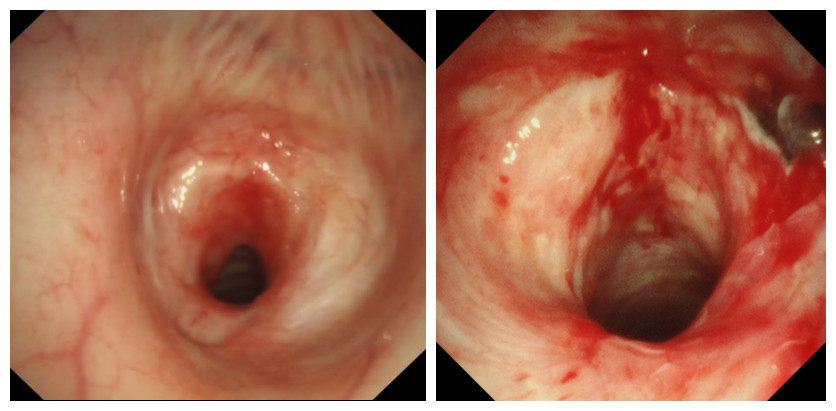

支气管镜显示声门下气管狭窄处直径仅为5毫米左右。“严重复杂的气管狭窄治疗非常困难,需全面运用多种支气管镜介入治疗技术和手段,帮助他耐受长时间手术的气管插管麻醉。”牟向东说。结合患者的实际情况,牟向东决定用电子支气管镜球囊扩张及电烧冷冻治疗为他扩张气道。

治疗前                                                 治疗后

在手术室和麻醉科的配合下,麻醉医师采用喉罩气管插管建立麻醉下机械通气。牟向东在气管镜下应用Nd:YAG激光,由近及远逐渐烧灼消融气管内狭窄部分,间断应用“氩气刀”(APC)止血治疗,在应用冷冻探头清除气道内的坏死物后,使用气管球囊在气道内进行扩张。经过5次气道扩张后,患者气管管腔逐渐恢复通畅,为接下来的肠瘘手术麻醉打好了基础。